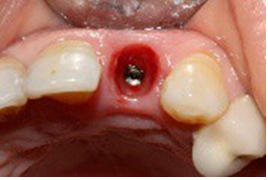

The 22 was then extracted atraumatically to preserve the bone on the vestibular side (Figure 6).

Figure 6. Atraumatic extraction of the 22

The surgical guide was placed and fixed (Figure 7) and we began the drilling sequence, to place a biotech 3,6/12 implant (Figure 8).

Figure 7. Placement of the surgical guide

Figure 8. Drilling sequence

After implant placement (Figure 9), the primary stability of the implant was satisfactory (greater than 35N), the provisional abutment was fixed (Figure 10) and a post-operative retroalveolar radiograph was taken for radiological control of the implant and adaptation of the provisional abutment (Figure 11).

PMMA resin was placed around the provisional abutment, and the occlusion was checked to ensure that the provisional prosthesis was underbite (Figure12).

Figure 9. Drilling sequence

Figure 12. Placement of PMMA resin and final result of provisional prosthesis